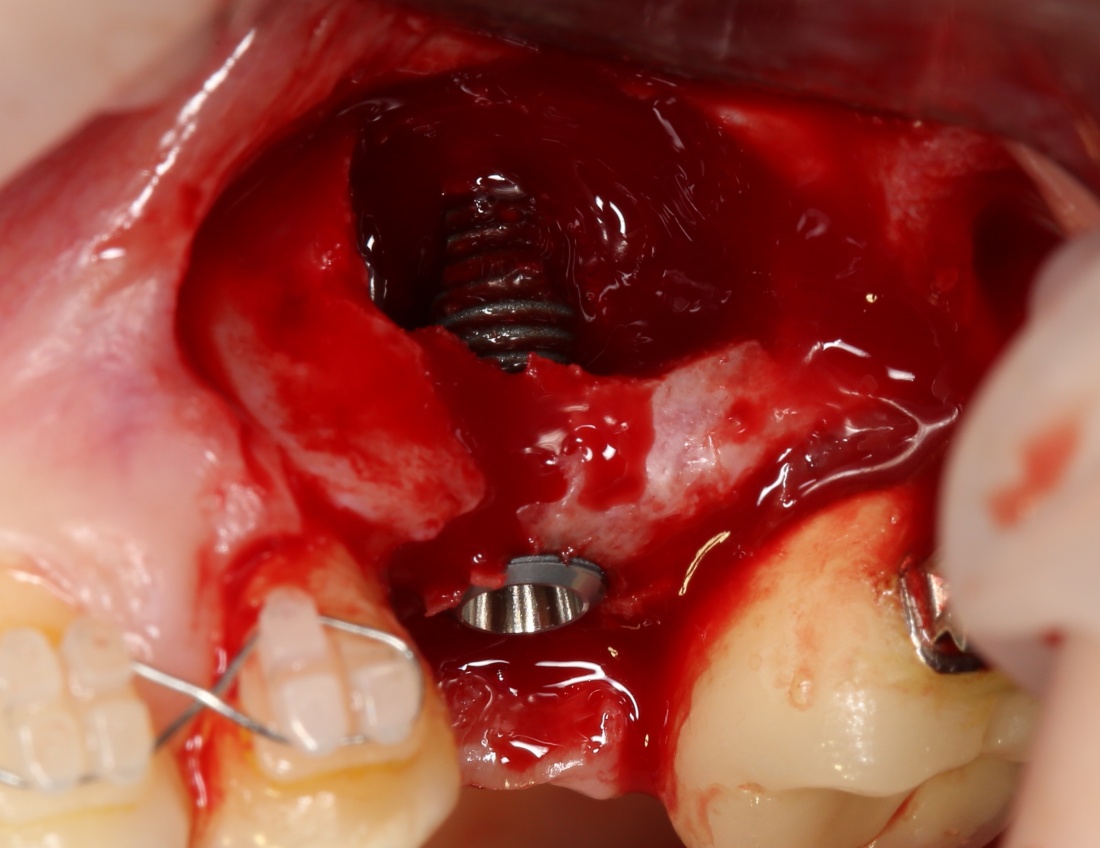

Однако, в этот раз я решил немного изменить план лекции. Теперь свою часть каждого из семинаров я буду посвящать какой-то конкретной операционной методике, рассказывая о ней чуть подробнее, чем принято говорить «бесплатно». И начнём мы с синуслифтинга, самой распространенной остеопластической операции в мире.

О том, почему открытый синуслифтинг безопаснее закрытого. И почему при закрытом синуслифтинге я не рекомендую использовать биоматериалы:

Каковы показания к открытому синуслифтингу? Когда его можно проводить совместно с установкой имплантов. а когда лучше сделать отдельным этапом?

Как правильно и аккуратно сделать доступ в верхнечелюстную полость? И как создать достаточное по объёму субантральное пространство?